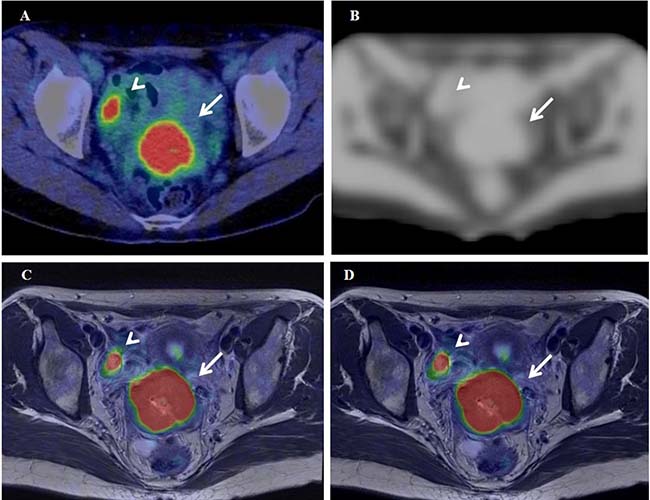

Representative cases of cervical cancer and oropharyngeal cancer are shown in Figures 5 and 6, respectively. Textural features were extracted using 64 bins (fixed bin width of 0.4 SUV) in these cases.

Figure 5: 18F-FDG PET/CT (A), the MRAC map (B), and PET/MR0-2min- and PET/MR0-10min-T2WI fused images (C and D) of a 37-year-old woman with stage IB2 cervical cancer. Arrows and arrowheads show the primary tumor and normal right ovary, respectively.

Figure 5A–5D show 18F-FDG PET/CT, the MR-AC map, and PET/MR0–2 min- and PET/MR0–10 min-T2WI fused images of a 37-year-old woman with stage IB2 cervical cancer (#6 in Table 2), respectively. SUV of 14.4 on delayed PET/MR0–2 min images was significantly higher (24%) than that of 11.6 on early PET/CT images. The Dixon-based MR-AC map (Figure 5B) did not assign the appropriate attenuation coefficient (μ value) to the pelvic bones, which may have resulted in insufficient AC underestimating tracer uptake on PET/MR images. However, SUV was markedly higher on PET/MR0–2 min images than on PET/CT images in the cervical cancer patient, possibly because the biological factor (SUV increase in the primary tumor at a delayed scan period) was markedly larger than the underestimation of tracer uptake by MR-AC. The differences (|% difference|) observed in TMR, skewness, kurtosis, entropy, homogeneity, SRE, and LRE between PET/CT and PET/MR0–2 min were 10%, 10%, 2%, 3%, 0%, 1%, and 7%, respectively.